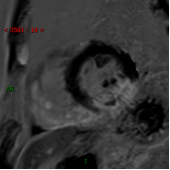

心脏增强磁共振(CMR)

心脏增强磁共振(CMR)是一种评估心肌健康状况的检查方法。虽然CMR无法直接观察冠状动脉的病变情况,但它能够对心肌的功能、结构和血流灌注提供详细的信息。CMR对于判断心肌是否存在缺血、纤维化、损伤等具有非常高的敏感性,因此它常用于冠心病发作后的恢复期评估,帮助医生判断心脏的恢复情况。此外,CMR还可以无创地评估心脏的收缩功能,适用于需要长期跟踪心脏健康状况的患者。

然而,CMR也有其局限性。首先,CMR对于冠脉狭窄的判断没有冠脉CTA那么精准,

因此不太用于冠心病的早期筛查。其次,由于CMR检查时间较长,且需要患者保持长时间静止,这对一些体弱或焦虑的患者来说,可能会增加检查的难度。

T2 STIR BB

PISR 10min